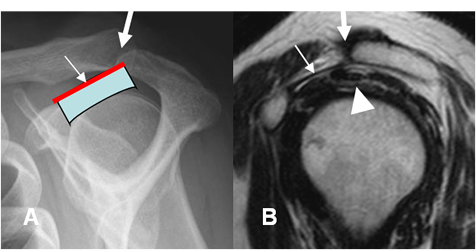

Fig 80 A. Arco coracoacromial normal.

A: Rx oulet, B y C: RM sagital en T2. Componentes del arco coracoacromial: Articulación acromioclavicular (Flecha gruesa), ligamento coracoacromial (Flecha delgada) y tendón del SE (Punta de flecha).